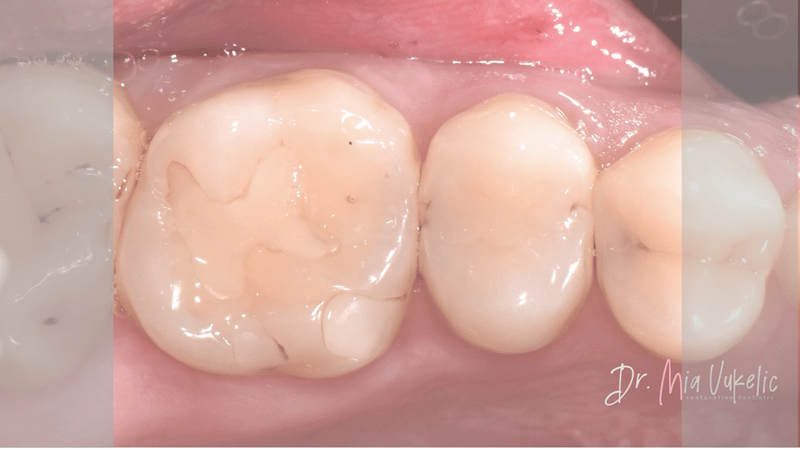

Esthetische benadering van een klasse II-restauratie (casusverslag) - Dr. Mia Vukelić

De patiënt bezocht de kliniek voor een jaarlijkse controle. Uit het klinisch en röntgenonderzoek bleek een secundaire cariëslaesie op het occlusale vlak van gebitselement 26 en twee cariëslaesies op de distale vlakken van gebitselement 24 en 25. De patiënt meldde geen specifieke symptomen. De voorgeschreven behandeling bestaat uit het aanbrengen van een klasse I-restauratie op gebitselement 26 en klasse II-restauraties op gebitselement 24 en 25.